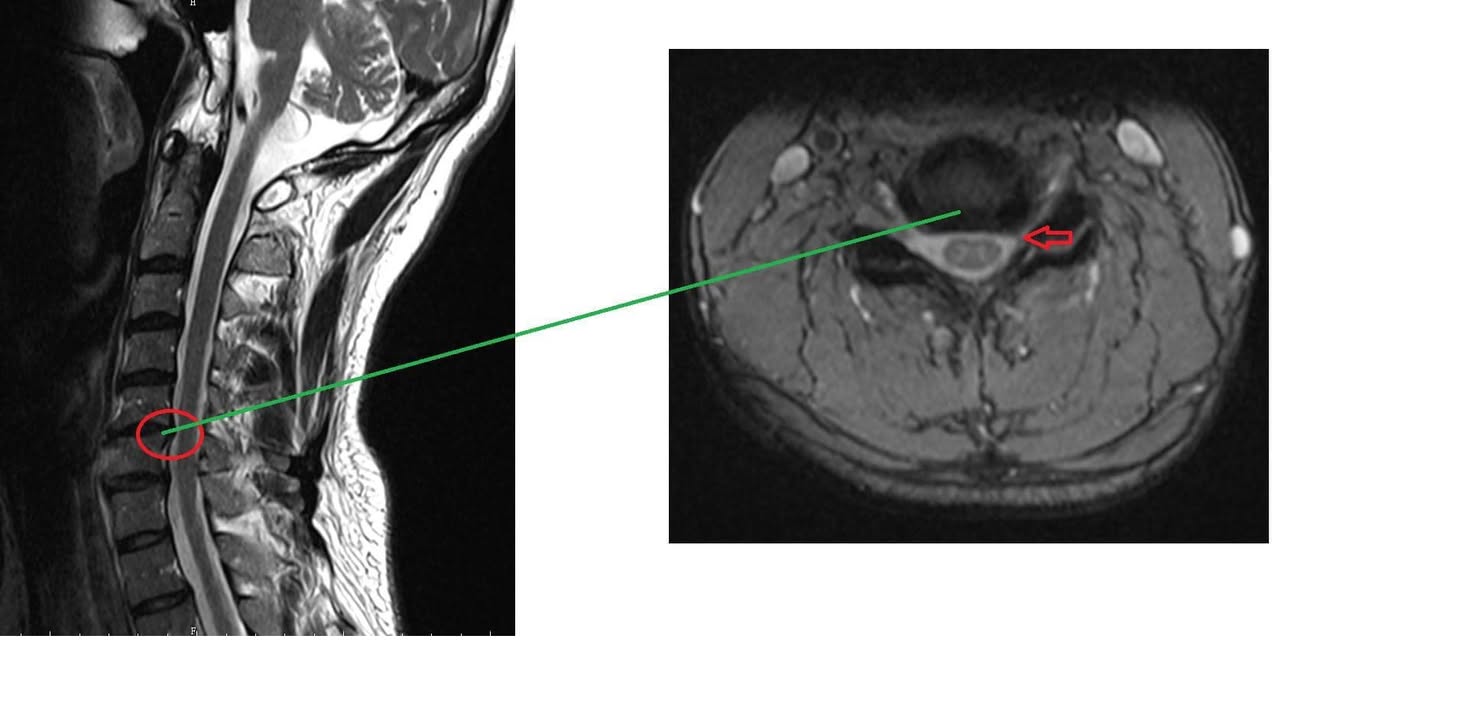

台北士林區詹先生抱怨1年前車禍受傷,先在中醫診所針灸三個月,又在新光醫院做整整1年的電療跟熱療,剛事故痛到手麻又沒力,才又去拍攝核磁共振,神外醫師看完片子建議開刀,由於患者畏懼開刀,就展開長達一年的中西醫復健,大約改善七成,但是每次平躺縮下巴頭旋轉就會強烈誘發左邊上臂痛,甚至手麻,就只剩這點一直沒改善⋯⋯⋯⋯⋯⋯

🆘診斷:神經根型頸椎病C5~C6

⭕️評估:患者手臂跟肩膀沒萎縮,肌力目前都正常,握力也沒問題,腳走路還沒問題,也沒有步態不穩的情況,也沒有肌反射增加,下肢肌肉張力正常,膝反射及足根反射正常,Babinski reflex正常,判斷中等程度神經根壓迫,還沒到嚴重脊髓病變,不過為了安心起見,先安排兩週治療,如果都沒有任何進步可以考慮新光醫院進行神外手術,或者疼痛科神經阻斷術

先說結論!嚴重頸椎壓迫特別是中老年人,如果發現四肢已經開始僵硬或行動不良,很像失速列車裡面那種殭屍走路,如果是這種患者,強烈建議給神經外科手術!但至於是否會完全恢復呢?答案是很困難,頸部脊髓MRI如果嚴重壓迫病變,這表示頸脊髓發生不可逆之病變,這類患者症狀當然只有進步而無法完全復原,問題是很多中老年人很長期依賴止痛藥跟推拿,通常這種患者來診都已經很嚴重了,能夠恢復到免強日常生活自理都很不錯了